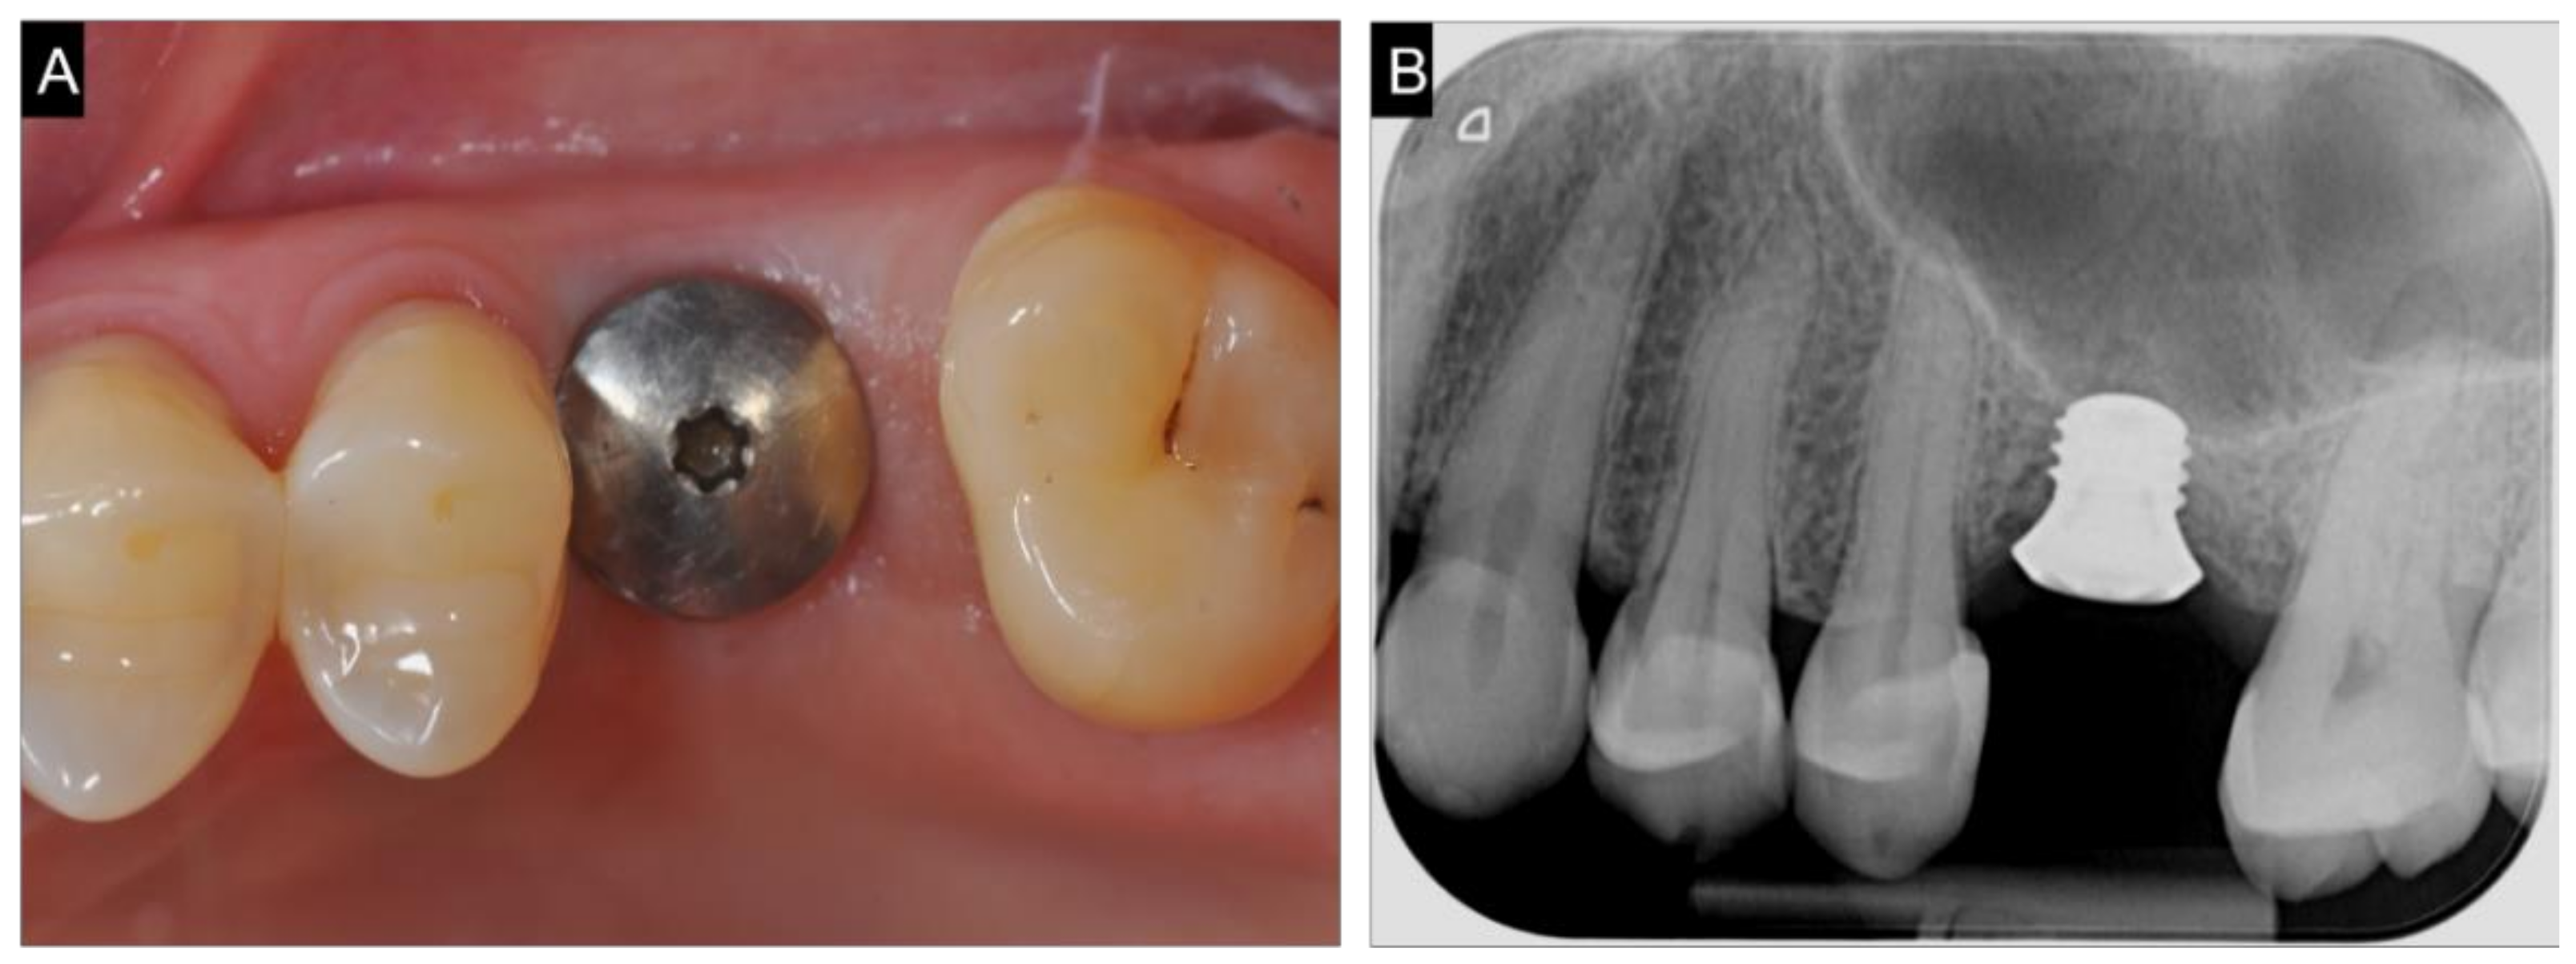

2.2. Surgical and Prosthetic Procedure

3. Results